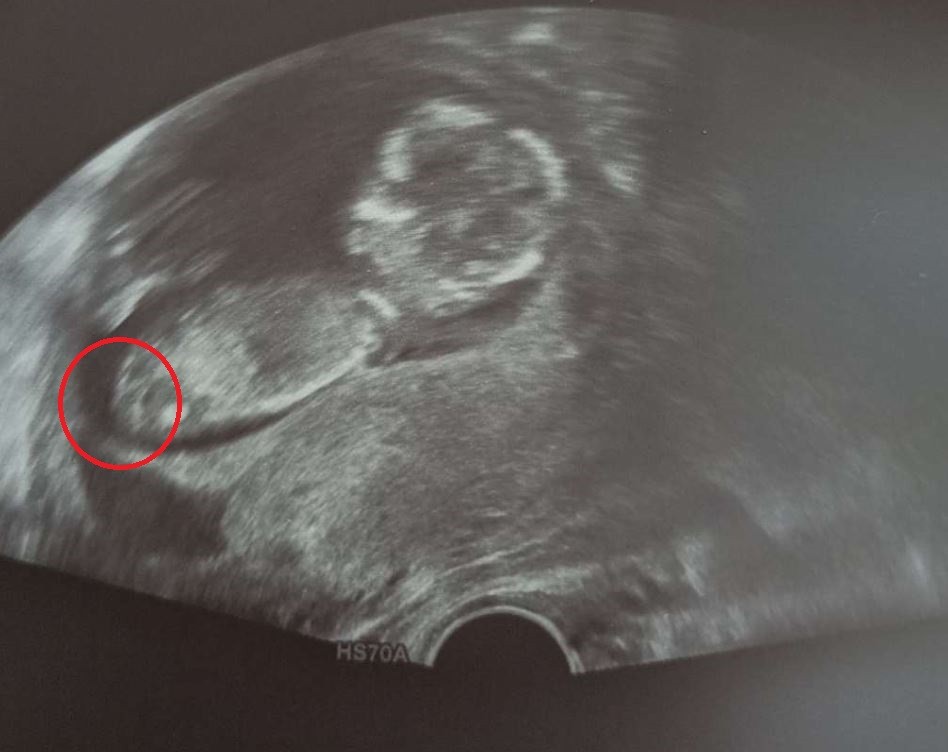

Z takiego zdjęcia możemy zobaczyc profil dzidziolka. Zdjecie narządów przeważnie jest to z pespektywy od dołu. Także cierpliwość, aż zechce pokazać co tam ma.Hej kobietki widać coś waszym zdaniem?

I już Ci określili płeć?A gdzie tu widzisz zdjęcie miejsca płciowe bo ja nie widzę żadnych poza miednicą która jest i u kobiet i u mężczyzn?